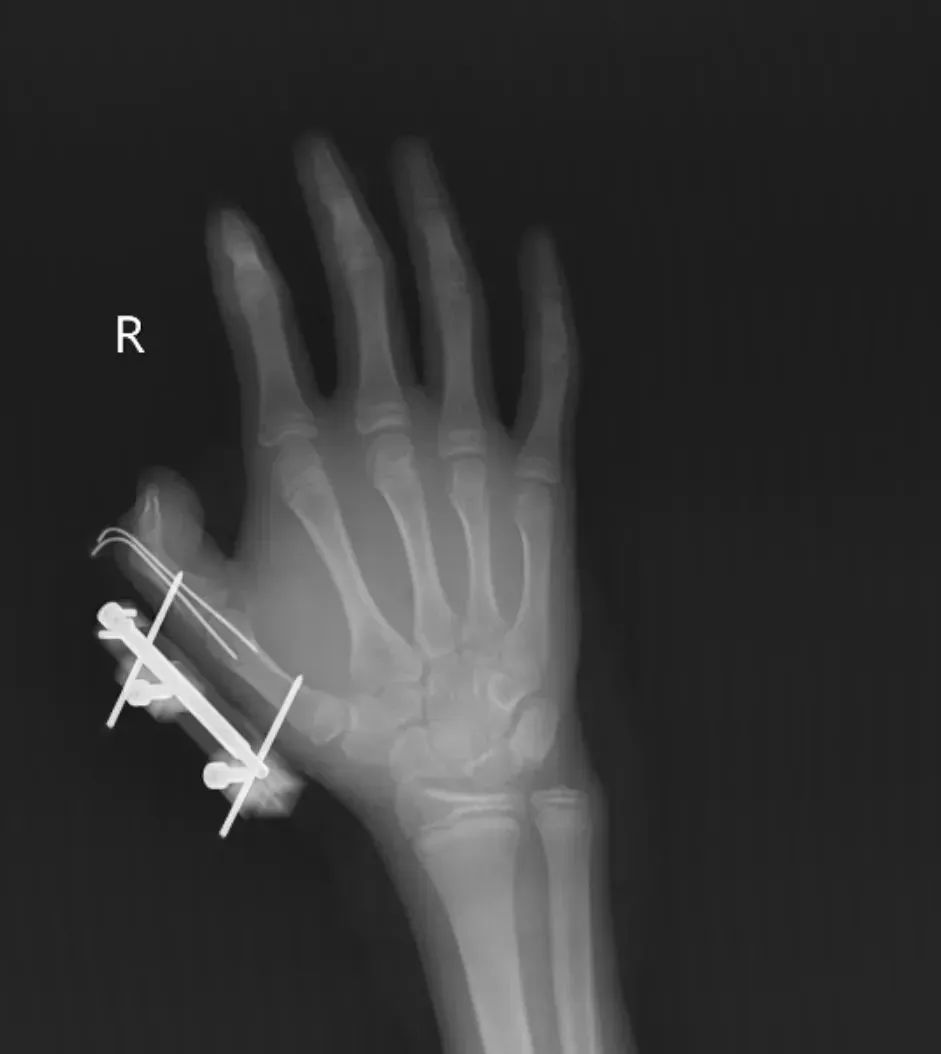

突然,密封袋里的干冰发生爆炸,维维的右手瞬间鲜血直流,拇指虎口处被撕开一道约10厘米的伤口,深可见骨,肌肉组织断裂外露,还伴随着拇指骨折、关节脱位,整个拇指完全失去知觉。

见状,家人赶紧带他到当地医院包扎,随后因伤情严重紧急转往大医院。经治疗,维维的拇指保住了,但后续还需长期康复训练,才能慢慢恢复手部精细动作功能。